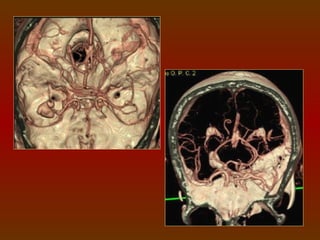

CÍRCULO OU POLÍGONO DE WILLIS

É um círculo de artérias que suprem o cérebro. Foi nomeado em

CIRCULAÇÃO SANGUÍNEA DO CÉREBRO

O sangue chega ao cérebro através das artérias vertebrais e

das artérias carótidas internas, que se comunicam através do

polígono de Willis, este é uma anastomose arterial que fornece o

suprimento sangüíneo para os hemisférios cerebrais, sendo

formado pelas artérias cerebrais anteriores e posteriores, artérias

comunicantes anterior e posteriores e pela carótida interna.

COMPONENTES

 Artéria cerebral anterior (direita e esquerda).

 Artéria comunicante anterior.

 Artéria carótida interna (direita e esquerda).

 Artéria cerebral posterior (direita e esquerda).

 Artéria comunicante posterior (direita e esquerda).

IMPORTÂNCIA FISIOLÓGICA

O arranjo das artérias no

Polígono   de    Willis    cria uma

redundância na circulação cerebral.

Se uma parte do círculo estiver

bloqueada ou estreitada (estenose),

ou se uma das artérias que suprem o

polígono    está     estreitada  ou

bloqueada, o fluxo sanguíneo dos

outros vasos sanguíneos podem

muitas vezes preservar a perfusão

cerebral .

ESTUDO DO POLÍGONO DE WILLIS

 1 mm espessa X 1 mm incremento.

 Em média 100 ml de contraste, a 3ml/s.

A marcação vai da

base do seio

esfenoidal ao topo

do corpo caloso.